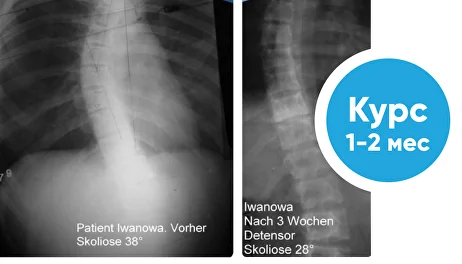

Лечение сколиоза

Уменьшение дуги сколиоза с 38 до 28 градусов за 2 месяца регулярных процедур вытяжения на мате Детензор